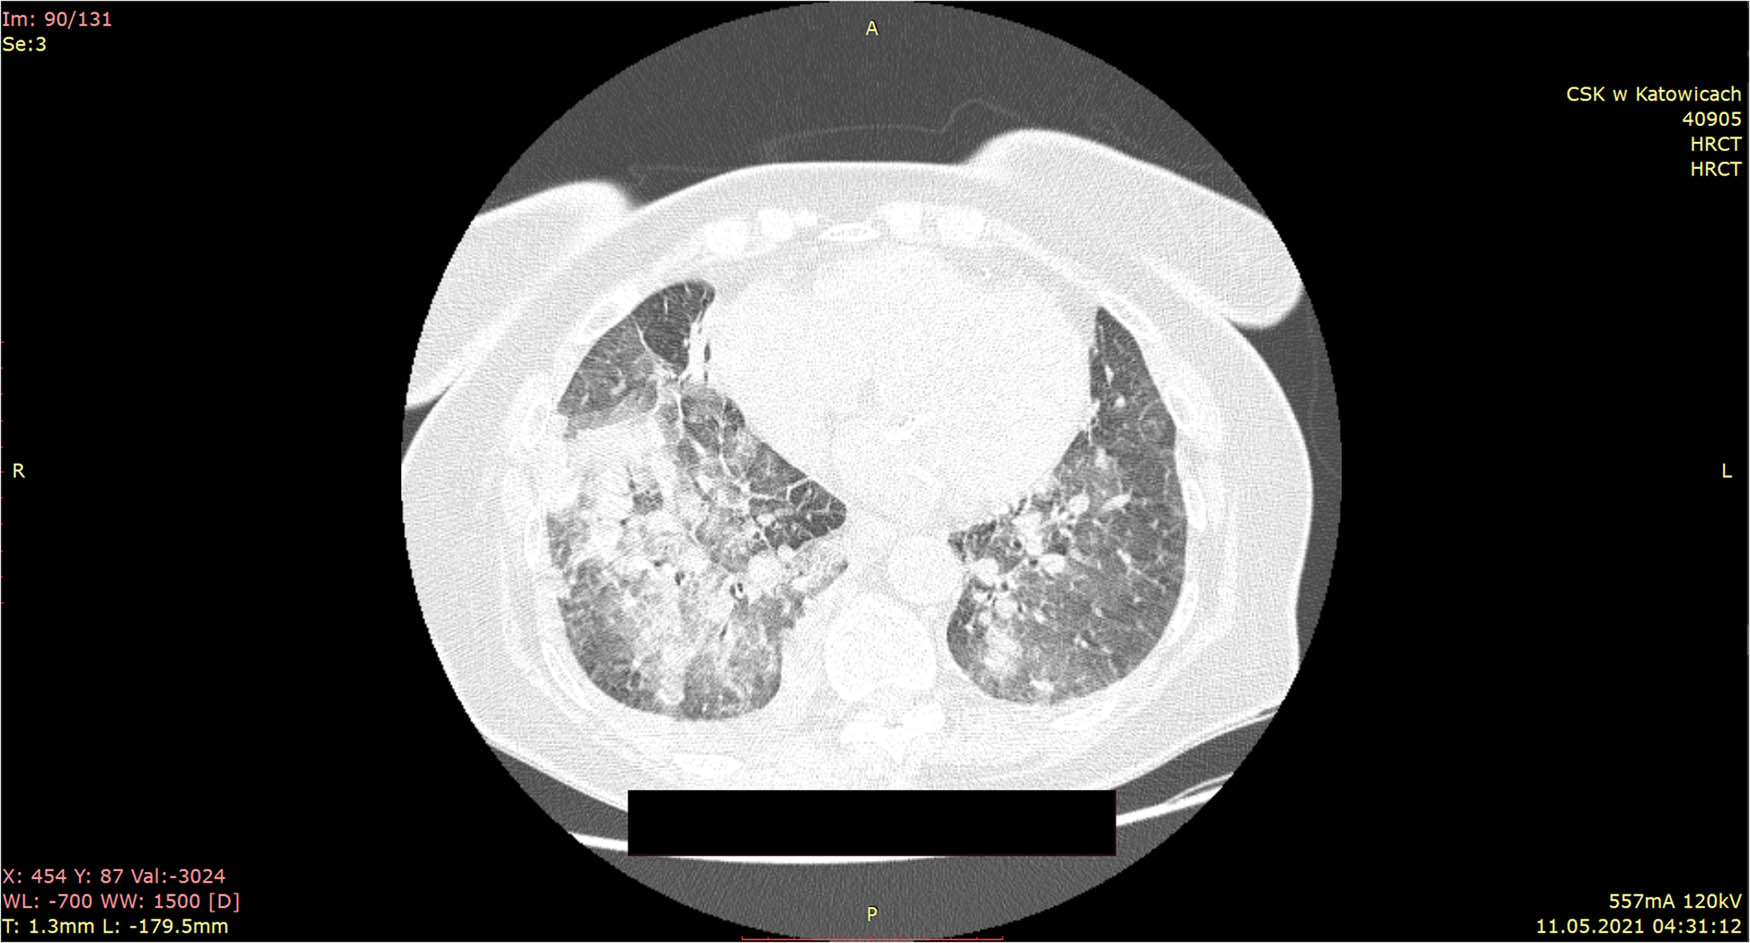

Due to reported symptoms and laboratory results, COVID-19 was suspected. In order to assess the severity of pneumonia, it was decided to perform lung HRCT. In HRCT bilateral, superimposed air space consolidations with GGO in lowers and uppers lobes, more marked on right were described. Moreover, thickening of the interlobular septa was observed. There were mediastinal hilar lymphadenopathy and bilateral pleural effusion. The lesions accounted for 48% of the lungs. These HRCT findings were described as typical for COVID-19 pneumonia with a moderately advanced British Society of Thoracic Imaging (BSTI) score (Figure 1).

HRCT scans on hospital admission: bilateral, superimposed air space consolidations with GGO in lower and upper lobes, more marked on right are described.